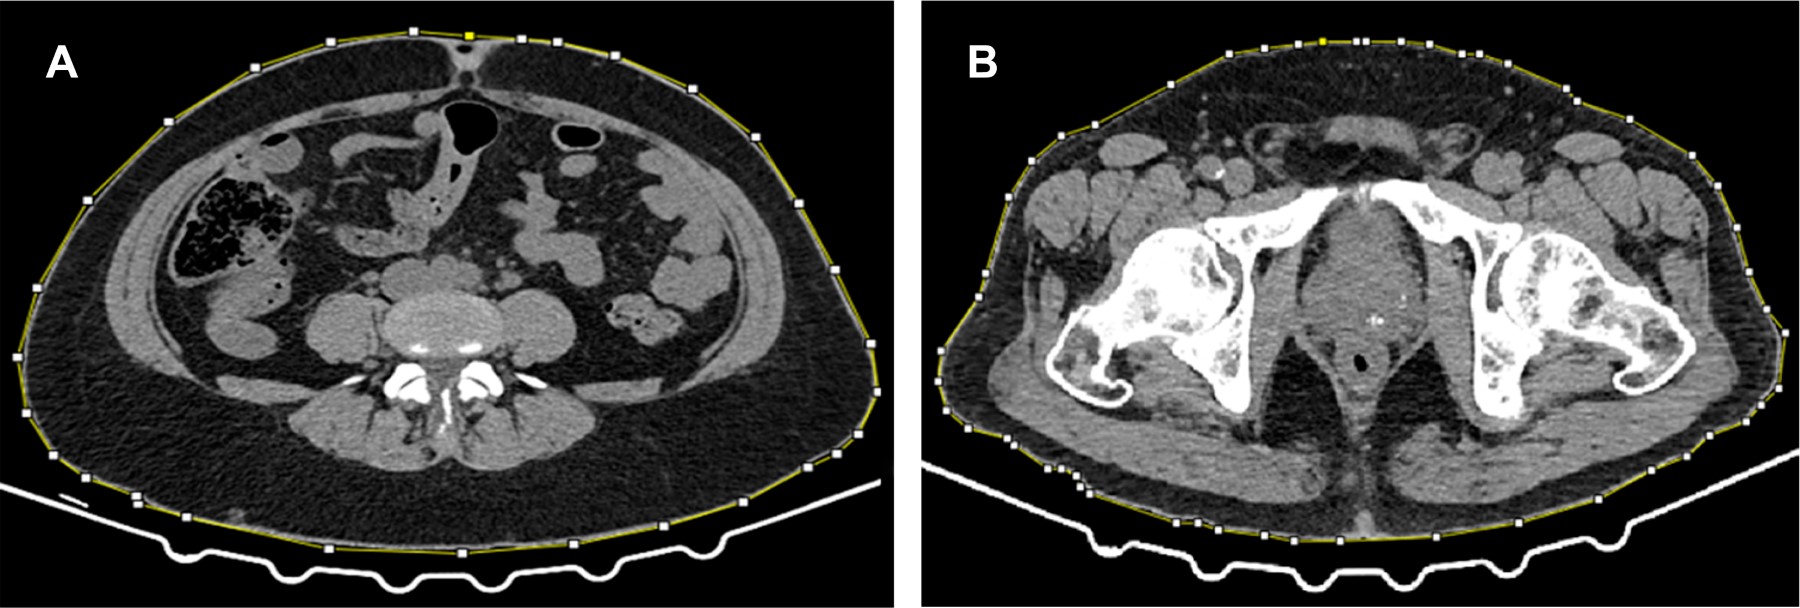

Comparison of visceral and subcutaneous adipose tissue of patients with hepatic steatosis in a Mexican population by axial computed tomography

Introduction: obesity, specifically visceral fat accumulation, has been related to metabolic diseases, such as hepatic steatosis. The study aims to compare the visceral and subcutaneous compartments of patients with hepatic steatosis to those with high waist circumference by computed tomography. Material and methods: an observational, cross-sectional, and analytical study was carried out in the Radiology and Imaging department of Hospital Angeles Mocel. Abdominal computed tomography studies of two groups of patients were analyzed. The umbilical level was identified to calculate visceral and subcutaneous fat area and the calculation of waist and hip circumference and waist/hip ratio. Results: there are statistically significant differences in excess visceral fat in patients with steatosis compared to patients with increased waist circumference. Conclusion: most of the patients with hepatic steatosis have visceral obesity by computed tomography, which is why it is a risk factor for its presentation.

Figure 1